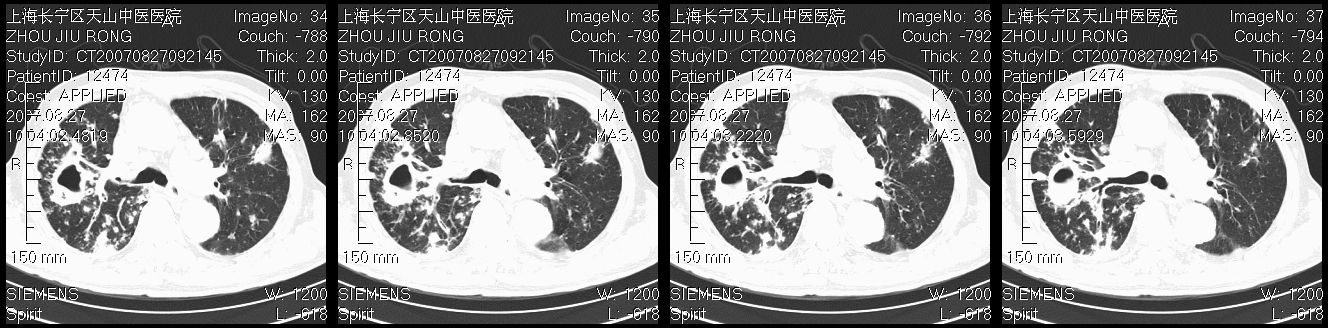

以下是引用zjzjr在2007-8-30 21:47:00的发言:[br]双肺弥漫性结节状、斑片状影,部分形成空洞,病灶以双肺上叶为著(符合结核发病部位),纵隔内见肿大淋巴结影。支持双肺继发性结核伴右上肺空洞形成。

以下是引用zjzjr在2007-8-30 21:47:00的发言:[br]双肺弥漫性结节状、斑片状影,部分形成空洞,病灶以双肺上叶为著(符合结核发病部位),纵隔内见肿大淋巴结影。支持双肺继发性结核伴右上肺空洞形成。

以下是引用gaoshengjiang在2007-8-31 10:24:00的发言:[br]双肺弥漫性斑片状影及多发空洞影,其间夹杂多量条索状影,胸膜肥厚、粘连并有结节状改变,纵隔多枚淋巴结肿大,考虑1双肺继发型肺结核合并感染?2韦格氏肉芽肿?[br] 支持!

以下是引用zjzjr在2007-8-30 21:47:00的发言:[br]双肺弥漫性结节状、斑片状影,部分形成空洞,病灶以双肺上叶为著(符合结核发病部位),纵隔内见肿大淋巴结影。支持双肺继发性结核伴右上肺空洞形成。

以下是引用zjzjr在2007-8-30 21:47:00的发言:[br]双肺弥漫性结节状、斑片状影,部分形成空洞,病灶以双肺上叶为著(符合结核发病部位),纵隔内见肿大淋巴结影。支持双肺继发性结核伴右上肺空洞形成。

以下是引用zjzjr在2007-8-30 21:47:00的发言:[br]双肺弥漫性结节状、斑片状影,部分形成空洞,病灶以双肺上叶为著(符合结核发病部位),纵隔内见肿大淋巴结影。支持双肺继发性结核伴右上肺空洞形成。